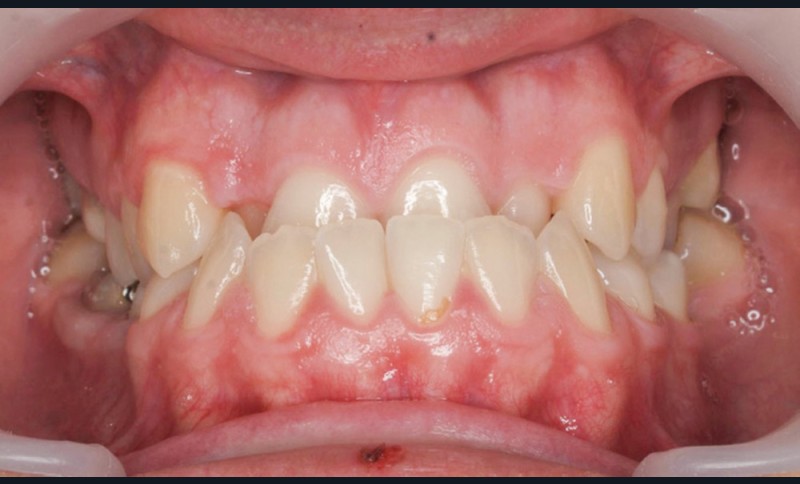

Diagnostic (fig. 1a-g)

La patiente présente une classe III squelettique dans un contexte hyperdivergent associée à une endoalvéolie maxillaire, un articulé inversé antérieur, une rétroversion incisive maxillaire, des rapports de classe I canine bilatérale, une absence de 16 et 36.

Au niveau esthétique, le profil est rectiligne. La lèvre supérieure est plus effacée, en retrait par rapport à la lèvre inférieure. De face et de profil, la mandibule paraît massive et le maxillaire effacé : le manque de soutien de la lèvre supérieure contribue à cette impression.

Le sourire est étroit, dégradé par les malpositions dentaires.

Au niveau fonctionnel, il existe un pro-glissement mandibulaire et un articulé inversé antérieur. Le profil téléradiographique montre en occlusion des rapports labiaux et un profil de classe III plus marqué que sur photographies.